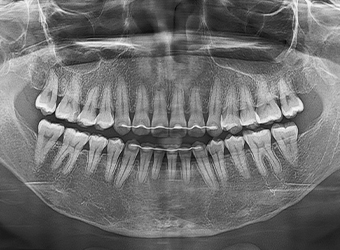

• X-ray, CT 등

방사선 촬영에서 핀이

보이고 싶지 않은 경우

치과 엑스레이 촬영 및 얼굴 CT촬영 시 얼굴핀이 드러나기 때문에 양악수술 이력이 밝혀지는 걸 원하지 않는 분들의 경우에도 핀제거수술을 고려할 수 있습니다.